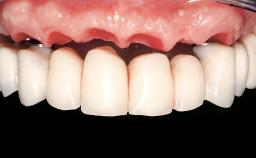

Immediate Loading of Six Implants in the Mandible and Six Implants in the Maxilla and Final Restoration with Full-Arch CAD/CAM Metal Framework FDPs Involving Digital Planning and Guided Surgery

Immediate loading of dental implants is increasingly popular with clinicians and patients. The idea of delivering a restoration directly after implant insertion,combined with a less invasive procedure (flapless protocol), has made treatment protocols involving dental implants more accessible to dentists and patients. However,immediate-loading concepts require sophisticated and exact planning. To facilitate this, conventional panoramic tomographs and periapical radiographs are often taken with the patient wearing a radiographic template simulating the preoperative prosthetic design. However, these radiographs do not provide all the necessary information. In addition, some protocols call for conventional surgical templates fabricated on the diagnostic cast. These will inform the bone drilling points and drill angles, but do not reference the underlying anatomical structures or provide exact 3-D guidance.

Abutment Type CAD/CAM

Prosthesis Type FDP